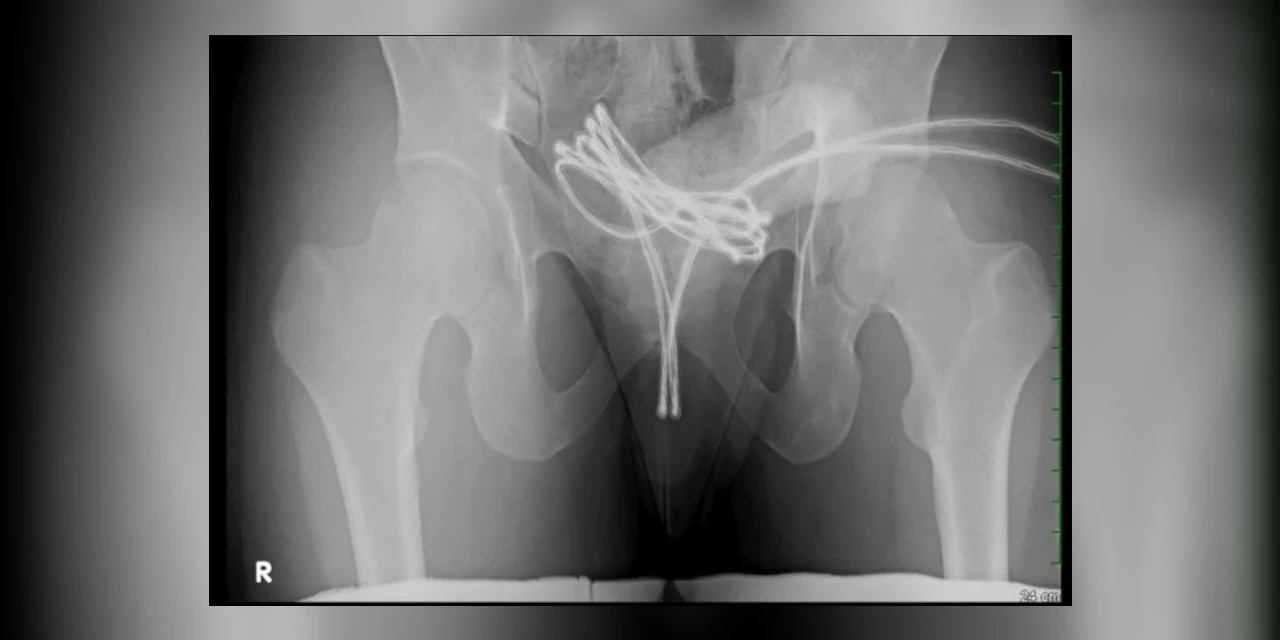

Após o cabo USB ser inserido na uretra, o objeto alcançou a bexiga do jovem.

O caso foi relatado por médicos da Universidade Drexel, nos EUAMédicos americanos descreveram, na edição de fevereiro da revista médica Cureus, o caso de um estudante universitário de 21 anos que inseriu um cabo USB na própria uretra para obter prazer sexual.

Ao perceber que o fio estava preso e que não conseguiria removê-lo por conta própria, o homem procurou ajuda médica em um hospital.Durante a consulta, ele revelou aos médicos que não foi a primeira vez que praticou o ato.